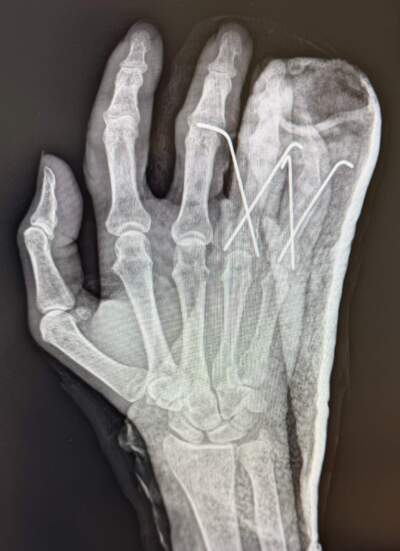

But something hurts; something hurts bad. I roll onto my back and lift my hand in the air. It's throbbing. Three of my fingers are headed in the wrong direction. My middle finger points off to the left, like a directional heading down a dead end. My ring finger looks like it's pointing in the opposite direction, my pinky is buckled in the middle, and my knee is screaming. My ribs ache.

At the ER, they tell me I need surgery, right away. Two fingers broken in several spots. The third finger is dislocated. I also have a broken rib. The ER doctor puts my fingers in a temporary cast (surgery will be days later). I wake to pain and a big fat cast that makes me look like I’m trying out for the role of Captain Hook.

It’s been six months since I had the surgery. My pinky is still bent in the middle, but thanks to months of PT, I have regained strength and dexterity in my right hand.